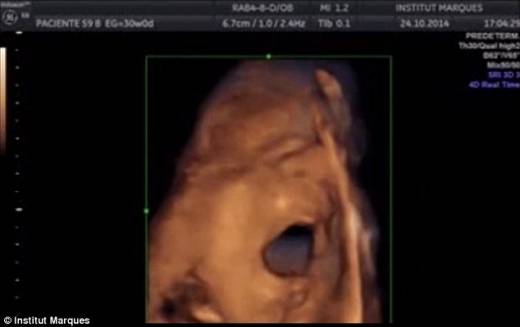

연구진은 임신 14~39주차에 해당하는 임신부의 질을 통해 일종의 ‘스피커’를 삽입한 뒤 음악을 재생했다. 그런 뒤 초음파로 태아의 움직임을 관찰한 결과 음악을 들은 태아가 혀와 입을 크게 움직이며 반응하는 것을 확인했다.

전체 태아의 전체의 87%는 입과 혀를 움직였고, 45%는 스스로 머리와 팔을 움직이는 모습을 보였으며, 10%는 혀를 입 밖으로 빼는 모습을 보였다.

이번 연구에서 가장 눈길을 끈 것은 태아가 고작 임신 16주에도 소리를 들을 수 있다는 사실과, 소리를 듣고 입과 혀를 움직이는 발성 동작을 보일 줄 안다는 사실이다. 이러한 발성동작은 신생아들이 언어를 습득하기 이전에 보이는 것과 같은 동작으로서, 구강구조를 통해 ‘노래’를 하듯 음악에 반응한다는 것을 확인한 것이다.